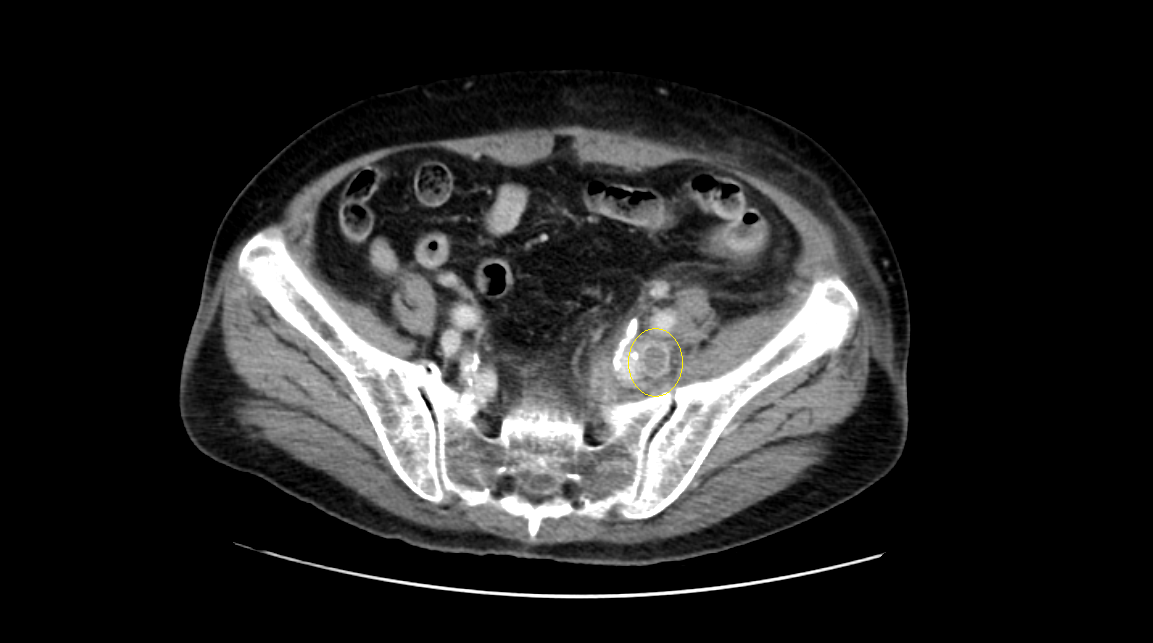

영상은 머리에 가까운 복부에서 다리 쪽으로 가는 순서로 나열하였다.

CT영상을 보면 좌측 장골정맥과 우측 장골동맥이 교차하는 지점에서부터 다리 말단 쪽으로 내려가며, 총장골정맥-외장골정맥-총대퇴정맥-표대대퇴정맥-오금정맥-경골정맥까지 혈전이 차있는 모습을 확인할 수 있었다.

Acute DVT, left CIV, EIV, IIV, CFV, SFV, popliteal and crural veins with compression of left CIV between vertebra and right CIA, c/w acute DVT with May Thurner syndrome.